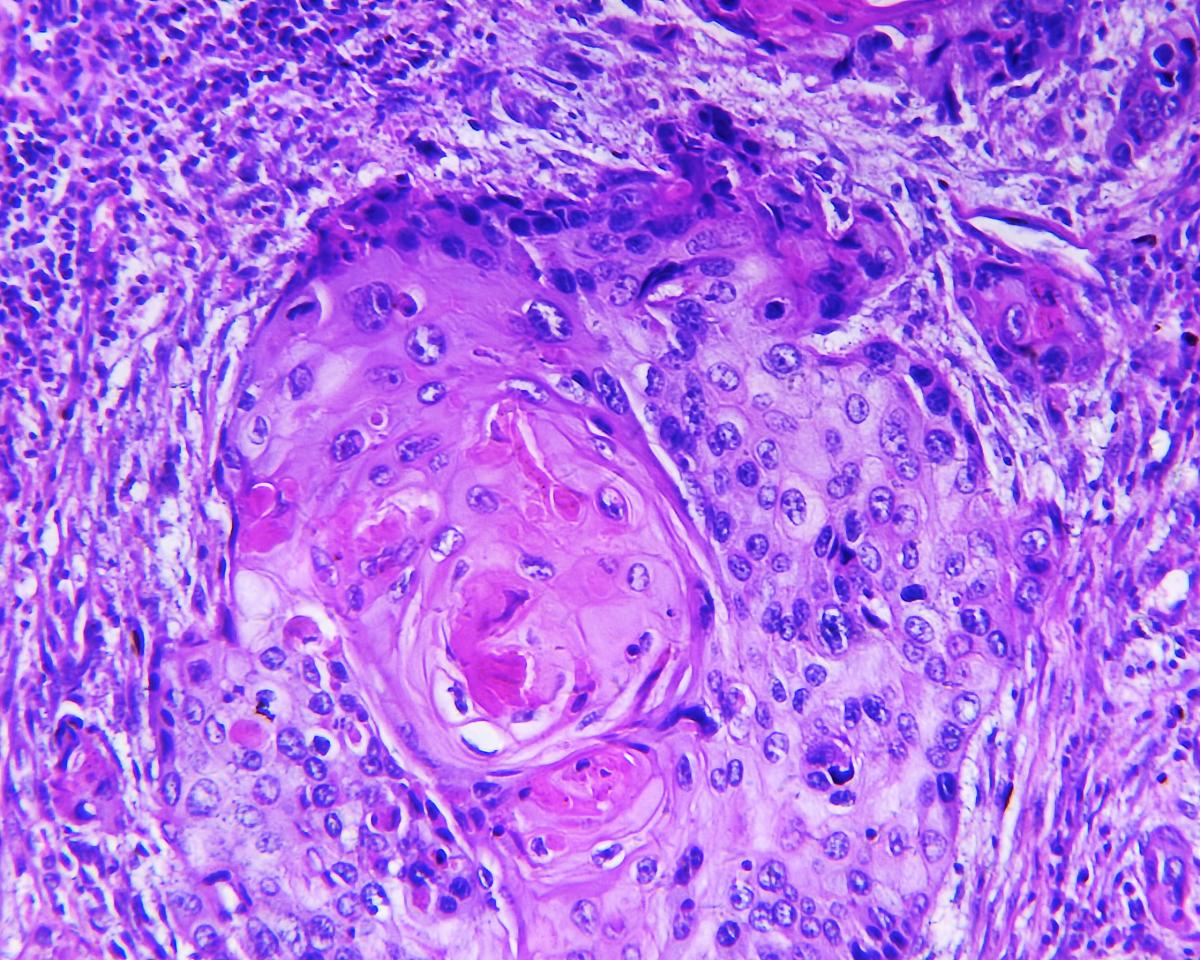

If the specimen has cancerous cells, the pathologist will tell us which type it is.

There are 2 main types of lung cancer: small cell cancer, and non-small cell cancer. They are described below.

Squamous Cell Carcinoma of the Lungs

Squamous cell carcinoma of the lung used to be more common, but now accounts for about 30% of non-small cell lung cancers in the Canada.

It usually starts in the main bronchial tubes, in the centre of the lungs.

This cancer is often discovered after people develop a nagging cough, cough up blood, or develop repeated respiratory infections.

Diagnosis

Paul's diagnosis was a type of non-small cell lung cancer: adenocarcinoma.